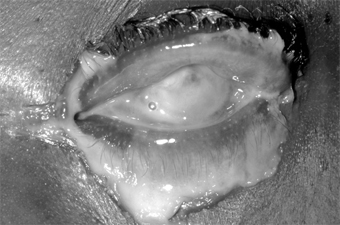

Chapter 5: Conjunctiva CONJUNCTIVITIS DUE TO INFECTIOUS AGENTS The types of conjunctivitis and their commonest causes are set forth in Tables 5-1 and 5-2. Because of its location, the conjunctiva is exposed to many microorganisms and other stressful environmental factors. Several mechanisms protect the surface of the eye from external substances: In the tear film, the aqueous component dilutes infectious material, mucus traps debris, and a pumping action of the lids constantly flushes the tears to the tear duct; the tears contain antimicrobial substances, including lysozyme and antibodies (IgG and IgA). Common pathogens that can cause conjunctivitis include Streptococcus pneumoniae, Haemophilus influenzae, Staphylococcus aureus, Neisseria meningitidis, most human adenovirus strains, herpes simplex virus type 1 and type 2, and two picornaviruses. Two sexually transmitted agents that cause conjunctivitis are Chlamydia trachomatis and Neisseria gonorrhoeae. Cytology of Conjunctivitis Damage to the conjunctival epithelium by a noxious agent may be followed by epithelial edema, cellular death and exfoliation, epithelial hypertrophy, or granuloma formation. There may also be edema of the conjunctival stroma (chemosis) and hypertrophy of the lymphoid layer of the stroma (follicle formation). Inflammatory cells, including neutrophils, eosinophils, basophils, lymphocytes, and plasma cells, may be seen and often indicate the nature of the damaging agent. The inflammatory cells migrate from the conjunctival stroma through the epithelium to the surface. They then combine with fibrin and mucus from the goblet cells to form the conjunctival exudate, which is responsible for the "mattering" on the lid margins (especially in the morning). The inflammatory cells appear in the exudate or in scrapings taken with a sterile platinum spatula from the anesthetized conjunctival surface. The material is stained with Gram's stain (to identify the bacterial organisms) and with Giemsa's stain (to identify the cell types and morphology). A predominance of polymorphonuclear leukocytes is characteristic of bacterial conjunctivitis. Generally, a predominance of mononuclear cells-especially lymphocytes-is characteristic of viral conjunctivitis. If a pseudomembrane or true membrane is present (eg, epidemic keratoconjunctivitis or herpes simplex virus conjunctivitis), neutrophils then predominate because of coexistent necrosis. In chlamydial conjunctivitis, neutrophils and lymphocytes are usually present in equal numbers. In allergic conjunctivitis, eosinophils and basophils are frequently present in conjunctival biopsies, but they are less common on conjunctival smears; eosinophils or eosinophilic granules are commonly found in vernal keratoconjunctivitis. High levels of proteins secreted by eosinophils (eg, eosinophil cationic protein) can be found in the tears of patients with vernal, atopic, or allergic conjunctivitis. Eosinophils and basophils are found in allergic conjunctivitis, and scattered eosinophilic granules and eosinophils are found in vernal keratoconjunctivitis. In all types of conjunctivitis, there are plasma cells in the conjunctival stroma. They do not migrate through the epithelium, however, and are therefore not seen in smears of exudate or of scrapings from the conjunctival surface unless the epithelium has become necrotic, as it may in trachoma; in this event, the rupturing of a follicle allows the plasma cells to reach the epithelial surface. Since the mature follicles of trachoma rupture easily, the finding of large, pale-staining lymphoblastic (germinal center) cells in scrapings strongly suggests trachoma. Symptoms of Conjunctivitis The important symptoms of conjunctivitis are a foreign body sensation, a scratching or burning sensation, a sensation of fullness around the eyes, itching, and photophobia. Foreign body sensation and a scratching or burning sensation are often associated with the swelling and papillary hypertrophy that normally accompany conjunctival hyperemia. If there is pain, the cornea is probably also affected. Pain of the iris or ciliary body is also suggestive of corneal involvement. Signs of Conjunctivitis (Table 5-2) The important signs of conjunctivitis are hyperemia, tearing, exudation, pseudoptosis, papillary hypertrophy, chemosis, follicles, pseudomembranes and membranes, granulomas, and preauricular adenopathy. Hyperemia is the most conspicuous clinical sign of acute conjunctivitis. The redness is most marked in the fornix and diminishes toward the limbus by virtue of the dilation of the posterior conjunctival vessels. (A perilimbal dilation or ciliary flush suggests inflammation of the cornea or deeper structures.) A brilliant red suggests bacterial conjunctivitis, and a milky appearance suggests allergic conjunctivitis. Hyperemia without cellular infiltration suggests irritation from physical causes such as wind, sun, smoke, etc, but may occur occasionally with diseases associated with vascular instability (eg, acne rosacea). Tearing (epiphora) is often prominent in conjunctivitis, the tears resulting from the foreign body sensation, the burning or scratching sensation, or the itching. Mild transudation also arises from the hyperemic vessels and adds to the tearing. An abnormally scant secretion of tears and an increase in mucous threads suggests keratoconjunctivitis sicca. Exudation is a feature of all types of acute conjunctivitis. The exudate is flaky and amorphous in bacterial conjunctivitis and stringy in allergic conjunctivitis. "Mattering" of the eyelids occurs upon awakening in almost all types of conjunctivitis, and if the exudate is copious and the lids are firmly stuck together, the conjunctivitis is probably bacterial or chlamydial. Pseudoptosis is a drooping of the upper lid secondary to infiltration of Müller's muscle. The condition is seen in several types of severe conjunctivitis, eg, trachoma and epidemic keratoconjunctivitis. Papillary hypertrophy is a nonspecific conjunctival reaction that occurs because the conjunctiva is bound down to the underlying tarsus or limbus by fine fibrils. When the tuft of vessels that forms the substance of the papilla (along with cellular elements and exudates) reaches the basement membrane of the epithelium, it branches over the papilla like the spokes in the frame of an umbrella. An inflammatory exudate accumulates between the fibrils, heaping the conjunctiva into mounds. In necrotizing disease (eg, trachoma), the exudate may be replaced by granulation tissue or connective tissue. When the papillae are small, the conjunctiva usually has a smooth, velvety appearance. A red papillary conjunctiva suggests bacterial or chlamydial disease (eg, a velvety red tarsal conjunctiva is characteristic of acute trachoma). With marked infiltration of the conjunctiva, giant papillae form which are flat-topped, polygonal, and milky-red in color. On the upper tarsus, they suggest vernal keratoconjunctivitis and giant papillary conjunctivitis with contact lens sensitivities; on the lower tarsus, they suggest atopic keratoconjunctivitis. Giant papillae may also occur at the limbus, especially in the area that is normally exposed when the eyes are open (between 2 and 4 o'clock and between 8 and 10 o'clock). Here they appear as gelatinous mounds that may encroach on the cornea. Limbal papillae are characteristic of vernal keratoconjunctivitis but are rare in atopic keratoconjunctivitis. Chemosis of the conjunctiva strongly suggests acute allergic conjunctivitis but may also occur in acute gonococcal or meningococcal conjunctivitis and especially in adenoviral conjunctivitis. Chemosis of the bulbar conjunctiva is seen in patients with trichinosis. Occasionally, chemosis may appear before there is any gross cellular infiltration or exudation. Follicles are seen in most cases of viral conjunctivitis, in all cases of chlamydial conjunctivitis except neonatal inclusion conjunctivitis, in some cases of parasitic conjunctivitis, and in some cases of toxic conjunctivitis induced by topical medications such as idoxuridine, dipivefrin, and miotics. Follicles in the inferior fornix and at the tarsal margins have limited diagnostic value, but when they are located on the tarsi (especially the upper tarsus), chlamydial, viral, or toxic conjunctivitis (following topical medication) should be suspected. The follicle consists of a focal lymphoid hyperplasia within the lymphoid layer of the conjunctiva and usually contains a germinal center. Clinically, it can be recognized as a rounded, avascular white or gray structure. On slitlamp examination, small vessels can be seen arising at the border of the follicle and encircling it. Pseudomembranes and membranes are the result of an exudative process and differ only in degree. A pseudomembrane is a coagulum on the surface of the epithelium, and when it is removed the epithelium remains intact. A membrane is a coagulum involving the entire epithelium, and if it is removed a raw, bleeding surface remains. Pseudomembranes or membranes may accompany epidemic keratoconjunctivitis, primary herpes simplex virus conjunctivitis, streptococcal conjunctivitis, diphtheria, cicatricial pemphigoid, and erythema multiforme major. They may also be an aftermath of chemical burns, especially alkali burns. Ligneous conjunctivitis is a peculiar form of recurring membranous conjunctivitis. It is bilateral, seen mainly in children, predominantly in females, and may be associated with other systemic findings, including nasopharyngitis and vulvovaginitis. Granulomas of the conjunctiva always affect the stroma and most commonly are chalazia. Other endogenous causes include sarcoid, syphilis, cat-scratch disease, and, rarely, coccidioidomycosis. Parinaud's oculoglandular syndrome includes conjunctival granulomas and a prominent preauricular lymph node, and this group of diseases may require biopsy examination to secure diagnosis. Phlyctenules represent a delayed hypersensitivity reaction to microbial antigen, eg, staphylococcal or mycobacterial antigens. Phlyctenules of the conjunctiva initially consist of a perivasculitis with lymphocytic cuffing of a vessel. When they progress to ulceration of the conjunctiva, the ulcer bed has many polymorphonuclear leukocytes. Preauricular lymphadenopathy is an important sign of conjunctivitis. A grossly visible preauricular node is seen in Parinaud's oculoglandular syndrome and, rarely, in epidemic keratoconjunctivitis. A large or small preauricular node, sometimes slightly tender, occurs in primary herpes simplex conjunctivitis, epidemic keratoconjunctivitis, inclusion conjunctivitis, and trachoma. Small but nontender preauricular lymph nodes occur in pharyngoconjunctival fever and acute hemorrhagic conjunctivitis. Occasionally, preauricular lymphadenopathy may be observed in children with infections of the meibomian glands. BACTERIAL CONJUNCTIVITIS Two forms of bacterial conjunctivitis are recognized: acute (and subacute) and chronic. Acute bacterial conjunctivitis may be self-limited when caused by certain microorganisms such as Haemophilus influenzae. The course may take up to 2 weeks if proper treatment is not given. Acute bacterial conjunctivitis may become chronic. Treatment with one of the many available antibacterial agents usually cures the condition in a few days. Purulent conjunctivitis caused by Neisseria gonorrhoeae or Neisseria meningitidis may lead to serious ocular complications if not treated early. Clinical Findings A. Symptoms and Signs: The organisms listed in Table 5-1 account for most cases of bacterial conjunctivitis. They produce bilateral irritation and injection, a purulent exudate with sticky lids on waking, and occasionally lid edema. The infection usually starts in one eye and is spread to the other by the hands. It may be spread from one person to another by fomites. 1. Hyperacute (and subacute) bacterial conjunctivitis-Purulent conjunctivitis- (caused by N gonorrhoeae, Neisseria kochii, and N meningitidis) is marked by a profuse purulent exudate (Figure 5-1). Meningococcal conjunctivitis may occasionally be seen in children. Any severe, profusely exudative conjunctivitis demands immediate laboratory investigation and immediate treatment. If there is any delay, there may be severe corneal damage or loss of the eye, or the conjunctiva could become the portal of entry for either N gonorrhoeae or N meningitidis, leading to septicemia or meningitis.

Figure 5-1: Gonococcal conjunctivitis. Profuse purulent exudate. (Courtesy of L Schwab.) Acute mucopurulent (catarrhal) conjunctivitis often occurs in epidemic form and is called "pinkeye" by most laymen. It is characterized by an acute onset of conjunctival hyperemia and a moderate amount of mucopurulent discharge. The commonest causes are Streptococcus pneumoniae in temperate climates and Haemophilus aegyptius in warm climates. Less common causes are staphylococci and other streptococci. The conjunctivitis caused by S pneumoniae and H aegyptius may be accompanied by subconjunctival hemorrhages. H aegyptius conjunctivitis in Brazil has been followed by a fatal purpuric fever produced by a plasmid-associated toxin of the bacteria. Subacute conjunctivitis is caused most often by H influenzae and occasionally by Escherichia coli and Proteus species. H influenzae infection is characterized by a thin, watery, or flocculent exudate. 2. Chronic bacterial conjunctivitis-Chronic bacterial conjunctivitis- occurs in patients with nasolacrimal duct obstruction and chronic dacryocystitis, which are usually unilateral. It may also be associated with chronic bacterial blepharitis or meibomian gland dysfunction. Patients with floppy lid syndrome or ectropion may develop secondary bacterial conjunctivitis. Rare bacterial conjunctivitides may be caused by Corynebacterium diphtheriae and Streptococcus pyogenes. Pseudomembranes or membranes caused by these organisms may form on the palpebral conjunctiva. The rare cases of chronic conjunctivitis produced by Moraxella catarrhalis, the coliform bacilli, Proteus, etc, are as a rule indistinguishable clinically. B. Laboratory Findings: In most cases of bacterial conjunctivitis, the organisms can be identified by the microscopic examination of conjunctival scrapings stained with Gram's stain or Giemsa's stain; this reveals numerous polymorphonuclear neutrophils. Conjunctival scrapings for microscopic examination and culture are recommended for all cases and are mandatory if the disease is purulent, membranous, or pseudomembranous. Antibiotic sensitivity studies are also desirable, but empirical antibiotic therapy should be started. When the results of antibiotic sensitivity tests become available, specific antibiotic therapy can then be instituted. Complications & Sequelae Chronic marginal blepharitis often accompanies staphylococcal conjunctivitis except in very young patients who are not subject to blepharitis. Conjunctival scarring may follow both pseudomembranous and membranous conjunctivitis, and in rare cases corneal ulceration and perforation supervene. Marginal corneal ulceration may follow infection with N gonorrhoeae, N kochii, N meningitidis, H aegyptius, S aureus, and M catarrhalis; if the toxic products of N gonorrhoeae diffuse through the cornea into the anterior chamber, they may cause toxic iritis. Treatment Specific therapy of bacterial conjunctivitis depends on identification of the microbiologic agent. While waiting for laboratory reports, the physician can start topical therapy with an antimicrobial drug. In any purulent conjunctivitis in which Gram's stain shows gram-negative diplococci suggestive of Neisseria, both system and topical therapy should be started immediately. If there is no corneal involvement, a single intramuscular dose of ceftriaxone, 1 g, is usually adequate systemic therapy. If there is corneal involvement, a 5-day course of parenteral ceftriaxone, 1-2 g daily, is required. In acute purulent and mucopurulent conjunctivitis, the conjunctival sac should be irrigated with saline solution as necessary to remove the conjunctival secretions. To prevent spread of the disease, the patient and family should be instructed to give special attention to personal hygiene. Course & Prognosis Acute bacterial conjunctivitis is almost always self-limited. Untreated, it may last 10-14 days; if properly treated, 1-3 days. The exceptions are staphylococcal conjunctivitis (which may progress to blepharoconjunctivitis and enter a chronic phase) and gonococcal conjunctivitis (which when untreated can lead to corneal perforation and endophthalmitis). Since the conjunctiva may be the portal of entry for the meningococcus to the bloodstream and meninges, septicemia and meningitis may be the end results of meningococcal conjunctivitis. Chronic bacterial conjunctivitis may not be self-limited and may become a troublesome therapeutic problem. CHLAMYDIAL CONJUNCTIVITIS 1. TRACHOMA Trachoma is one of the most ancient of known diseases. It was recognized as a cause of trichiasis as early as the 27th century BC and affects all races. With 300-600 million of the world's population afflicted, it is one of the most common of all chronic diseases. Its regional variations in prevalence and severity can be explained on the basis of variations in the personal hygiene and standards of living of the world's peoples, the climatic conditions under which they live, the prevailing age at onset, and the frequency and type of the prevailing concomitant bacterial eye infections. Blinding trachoma occurs in many parts of Africa, some parts of Asia, among Australian aborigines, and in northern Brazil. Communities with milder nonblinding trachoma occur in the same regions and in some areas of Latin America and the Pacific Islands. Trachoma is usually bilateral. It is spread by direct contact or fomites, usually from other family members (siblings, parents), who should also be examined for the disease. Insect vectors, especially flies and gnats, may play a role in transmission. The acute forms of the disease are more infectious than the cicatricial forms, and the larger the inoculum the more severe the disease. Spread is often associated with epidemics of bacterial conjunctivitis and with the dry seasons in tropical and semitropical countries. Clinical Findings A. Symptoms and Signs: Trachoma is initially a chronic follicular conjunctivitis of childhood that progresses to conjunctival scarring. In severe cases, inturned eyelashes occur in early adult life as a result of severe conjunctival scarring. The constant abrasion of inturned lashes and a defective tear film lead to corneal scarring, usually after the age of 50 years. The incubation period of trachoma averages 7 days but varies from 5 to 14 days. In an infant or child, the onset is usually insidious, and the disease may resolve with minimal or no complications. In adults, the onset is often subacute or acute, and complications may develop early. At onset, trachoma often resembles other bacterial conjunctivitis, the signs and symptoms usually consisting of tearing, photophobia, pain, exudation, edema of the eyelids, chemosis of the bulbar conjunctiva, hyperemia, papillary hypertrophy, tarsal and limbal follicles, superior keratitis, pannus formation, and a small, tender preauricular node. In established trachoma, there may also be superior epithelial keratitis, subepithelial keratitis, pannus, superior limbal follicles, and ultimately the pathognomonic cicatricial remains of these follicles, known as Herbert's pits-small depressions in the connective tissue at the limbocorneal junction covered by epithelium. The associated pannus is a fibrovascular membrane arising from the limbus, with vascular loops extending onto the cornea. All of the signs of trachoma are more severe in the upper than in the lower conjunctiva and cornea. To establish the presence of endemic trachoma in a family or community, a substantial number of children must have at least two of the following signs: